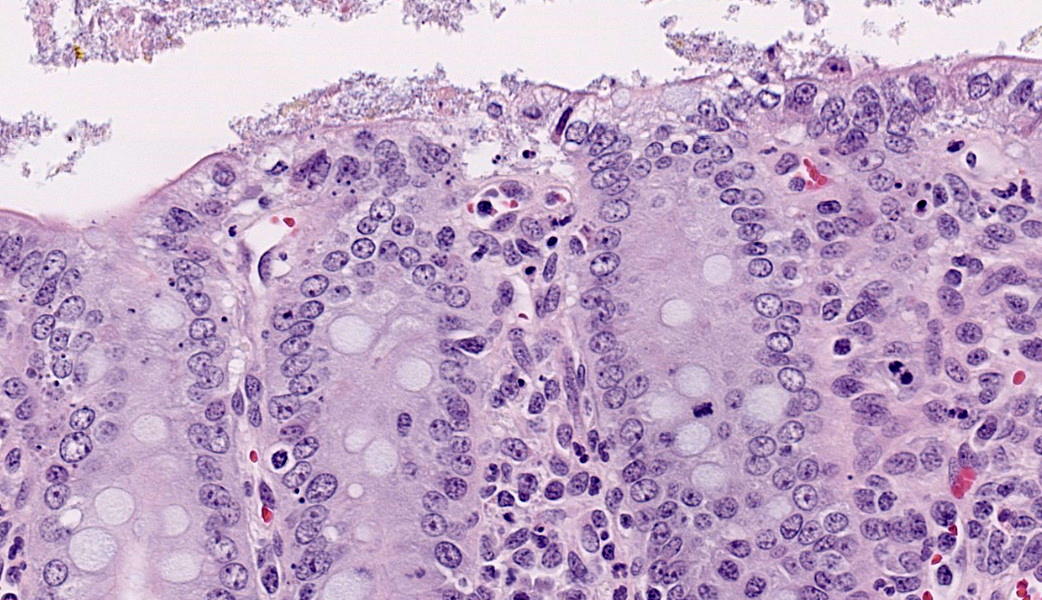

Ileum: In several sections, there is moderate multifocal blunting and fusion of villi with a crypt: villus ratio of 1:1. Apical enterocytes are often moderately attenuated with loss of the brush border and reduced apical cytoplasm. In some sections, these cells have a profound number of intracellular but extracytoplasmic 1-2 um circular eosinophilic apicomplexan organisms with 0.5 um basophilic nuclei (Cryptosporidium sp.). In other sections, these cells contain numerous larger apicomplexans with varied life-stages apparent including: 10 x 5 um curvilinear binucleate meronts (type I meronts), 4 x 12 um curvilinear uninucleate merozoites (type I merozoites), 9 x 6 um ovoid multinucleate meronts (type II meronts), multiple 3 x 12 um curvilinear uninucleate merozoites joined at their base by a residual body (type II merozoites), a 12um diameter circular lightly basophilic microgamont filled with numerous peripheral uninucleate deeply basophilic microgametes, or a 18 um diameter circular lightly basophilic macrogamont with a 8 um granular circular nucleus (macrogamont) (Cystoisospora suis). Rare crypts are ectatic, lined by moderately flattened, attenuated epithelium, and filled with cellular and karyorrhectic debris admixed with rare degenerate neutrophils (crypt abscesses). The associated lamina propria is often infiltrated by numerous eosinophils admixed with a few neutrophils. In one section, there is profound necrosis in Peyer’s patches, characterized by abundant karyorrhectic and cellular debris admixed with rare neutrophils, that often obscures typical follicular architecture. Similar changes are occasionally present in the overlying lamina propria, with marked lymphocytolysis and loss of proprial architecture. Vascular structures in all tunics are moderately congested, and macrophages occasionally aggregate around medium-caliber vessels in the submucosa.Spiral Colon: In both sections, there is moderate multifocal ulceration of the colonic mucosa characterized by loss of apical colonocytes with abundant cellular and karyorrhectic debris admixed with minimal fibrin and extravasated erythrocytes adhered to the exposed lamina propria. Adjacent colonocytes are often flattened, irregularly spaced, with reduced apical cytoplasm (attenuation). The associated lamina propria is often infiltrated by neutrophils and eosinophils admixed with necrotic debris and a few macrophages. Crypts within these areas are often ectatic, lined by mildly attenuated epithelium, and filled with either cellular and karyorrhectic debris admixed with degenerate neutrophils (crypt abscesses) or numerous eosinophils. Several other crypts are filled with up to 15 5 x 7 um pyriform to crescent-shaped protozoa with lightly basophilic cytoplasm and a faint nucleus (Suspect Trichomonads). The colonic lumen contains abundant cellular debris admixed with numerous colonies of basophilic bacteria with morphology ranging from coccoid to bacillary to filamentous, as well as rare 80 um circular flagellated protozoa with a prominent bean-shaped nucleus and a large cytoplasmic vacuole and abundant phagocytosed cellular debris (Suspect Balantidium coli). The submucosa is multifocally infiltrated by numerous macrophages admixed with lymphocytes and a small amount of karyorrhectic debris and these cells often aggregate around medium to large caliber vessels. Multifocally the cortical and medullary architecture of the mesenteric lymph node is effaced by abundant cellular and karyorrhectic debris (lymphocytolysis) admixed with rare infiltrating neutrophils and macrophages.

Ileum and colon (mediastinal lymph node, Peyer’s patches, and lamina propria): Lymphoid necrosis, multifocal, profound, subacute.Ileum: Atrophic enteritis, necrosuppurative and eosinophilic segmental, marked, subacute, with crypt abscesses and numerous intralesional apicomplexans with morphology consistent with Cryptosporidium spp. and Cystoisospora suis

- Ileum: Villar blunting, diffuse, marked with numerous intracytoplasmic, extracellular apicomplexan schizonts and gamonts consistent with Cryptosporidium sp., and intracytoplasmic, intracellular apicomplexan meronts, schizonts, and gamonts consistent with coccidiosis.